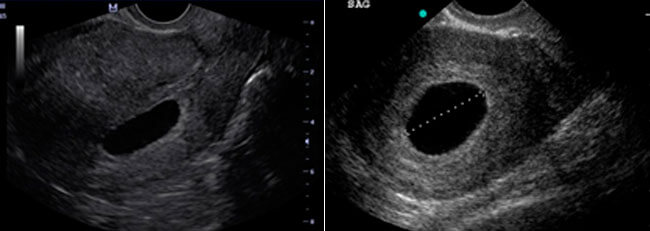

5-6 hepdelik embrionsyz tohum ýumurtgasy bolsa şeýle görünýär:

Bu ýagdaýa anembrioniýa diýilýär. Tohum ýumurtgasy boş. Edil towuk ýumurtga basyranda arasynda käbiriniň pak çykyşy ýaly boş. Bu duýgy bolsa ýerine düşmedik azap, myrat bolmadyk maksat ýaly ýürek gyýyjy. Foliý turşylygyny magniý, E witamini ýaly dürli derman serişdelerini ulanansyňyz. Zor bilenem bolsa, şowsuz göwreliligiň öňüni almak üçin dýufaston içensiňiz. Emma hemmesiniň netjesi – boşluk.